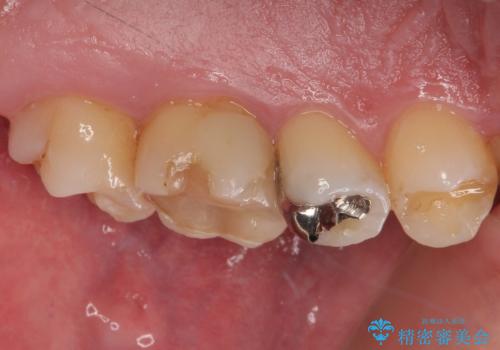

- 「奥歯がたまにしみるときがある」との主訴で来院された患者様です。

検査の結果、虫歯が非常に深く、通常であれば神経をすべて取り除く抜髄処置が必要な状態でした。

神経をすべて取り除いてしまうと歯の寿命が縮まってしまうため、感染している神経の一部を取り除く生活歯髄療法を行っていくことご提案しました。